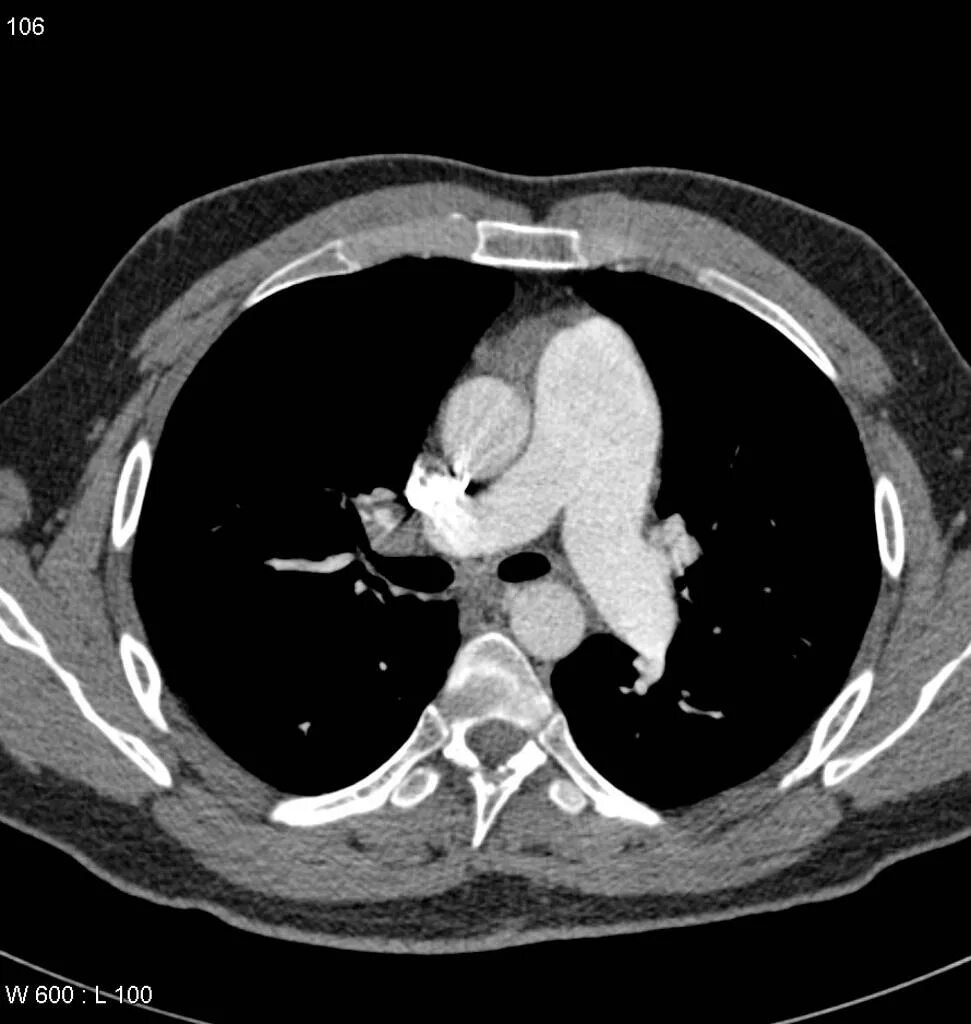

Легочный ствол на кт